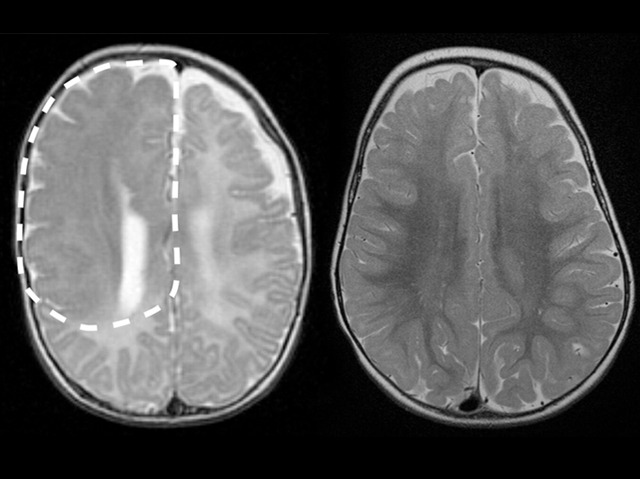

Our brain is the control centre for everything we do, think and feel. Malformations in the brain can be disastrous and leave the sufferer incapacitated. Hemimegalencephaly is a rare brain malformation in which one side of the brain is abnormally large, seen here highlighted by the dashed line on the left, and causes severe epileptic seizures. The deformity is caused by mutations in the genome of individual brain cells during development. Currently surgery is the most successful treatment for severe symptoms, but for some patients this can mean having the entire affected half of their brain removed. While the remaining healthy side of the brain may gradually take over functions that have been lost, the procedure is immensely invasive. Scientists are now investigating the gene mutations sustained by the developing brain cells in the hope of uncovering better ways to treat such debilitating conditions in the future.